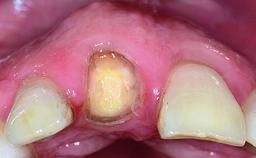

A healthy 23-year-old female patient was referred for a consultation on replacing tooth 21 with an implant-supported restoration. The patient had recently moved to the area and reported a history of endodontic and periodontal treatment for tooth 21. The tooth had been deemed non-restorable by her previous periodontist but since she was going to be moving, he recommended consulting to a dentist in her new city to continue her treatment. A review of her medical history yielded no significant findings and no known drug allergies. The analysis of her smile revealed a medium to high symmetrical smile line and a slightly discolored tooth 21.